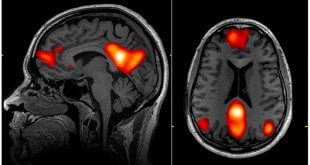

ادامهی نوشتهبرای خودخواهان، آینده مفهومی ندارد: شواهدی از تصویربرداری مغزی

نوروسافاری | مطالعه ی جدیدی که با استفاده از تصویربرداری های مغزی انجام شده است نشان می دهد افرادی که خود را خودپسند یا خودخواه می دانند، زمانی که در حال تفکر در مورد آینده هستند، هیچ افزایشی در بخشی از مغز آن ها به نام Ventromedial prefrontal cortex …